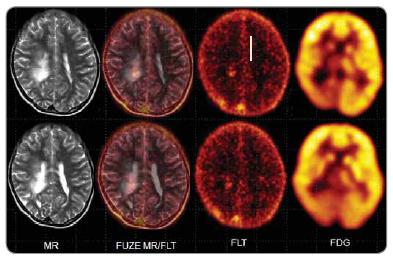

Od pozitronové emisní tomografie se v neuroonkologii požaduje odlišit benigní a maligní léze mozku, stanovit grading nádorů, určit nejvhodnější místo pro biopsii, tzv. PET-em navigovaná stereotaktická biopsie, stanovit reziduum nádoru po terapii, zjistit rekurenci nádoru, zjistit metastatické postižení mozku. Za tímto účelem je pro PET vyšetření mozku mimo 18F-fluoro-deoxy-glukózu (FDG), která tvoří základní radiofarmakum využívané pro vyšetření mozku, teoreticky možné využít množství různých neaktivních nosičů značených pozitronovými zářiči připravených v cyklotronu (18F, 11C, 13N,15O) nebo tzv. generátorových zářičů (68Ga, 82Rb). Většina non-FDG radiofarmak se však vzhledem k problémům souvisejícím s výrobou, distribucí nebo cenou využívají jenom v omezené míře, zejména v rámci výzkumných projektů. Mimo FDG se z alternativních radiofarmak v PET Centru Masarykova onkologického ústavu v Brně používají 18F- fluorothymidin a 11C-methionin. 18F-flurothymidin (FLT) je aktivně transportován TK1 v S-fázi mitotického cyklu a akumulace tohoto radiofarmaka koreluje oproti FDG s markerem proliferační aktivity Ki-67. FLT se v gliomech akumuluje cca 3krát méně než FDG, tumor/background ratio je však u FLT, vzhledem k minimální mitotické aktivitě ve zdravé mozkové tkáni, cca 3krát vyšší než u FDG. 11C-methionin ( MET) vykazuje výrazně vyšší akumulaci v lézích se zvýšenou proteosyntézou a vyšší vaskulární permeabilitou. Jeho výhodou je relativně nižší fyziologická akumulace v mozku ve srovnání s FDG. Potenciální využití tohoto radiofarmaka vidíme pro grading tumorů, zjištění relapsu po operaci nebo radioterapii, využití u stereotaktické biopsii a plánování radioterapie. Využití MET je omezené pro PET centra disponující ve své blízkosti cyklotronem, protože vzhledem ke krátkému fyzikálnímu poločasu 11C (20 min) není možné radiofarmaka značená 11C distribuovat na větší vzdálenost.

Základním radiofarmakem využívaným pro PET vyšetření mozku je FDG. Non-FDG radiofarmaka můžou významným způsobem doplnit PET vyšetření mozku v případech, kde FDG scan není jednoznačný.